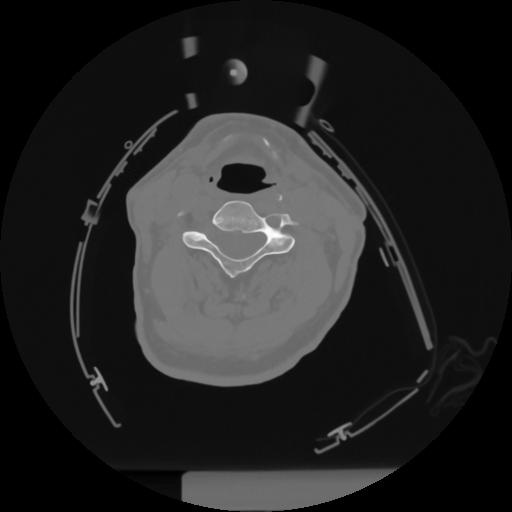

12 P.BLANDAS,,Vol,0.5,P.BLANDAS,,